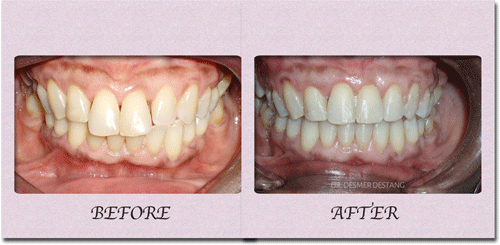

Protruded teeth (bucked teeth) happen when either the upper jaw is too far forward, the lower jaw is too far back, or a combination of both. Expert analysis allows us to determine the cause of the protrusion, and the most effective treatment plan.

With this type of bite, the front teeth are very protuded, and makes these delicate teeth highly prone to trauma, injury, and even premature tooth loss.

We have a number of different options and appliance types for correcting protruded teeth. The photos below illustrate protruded teeth, and the corrections in our patients.